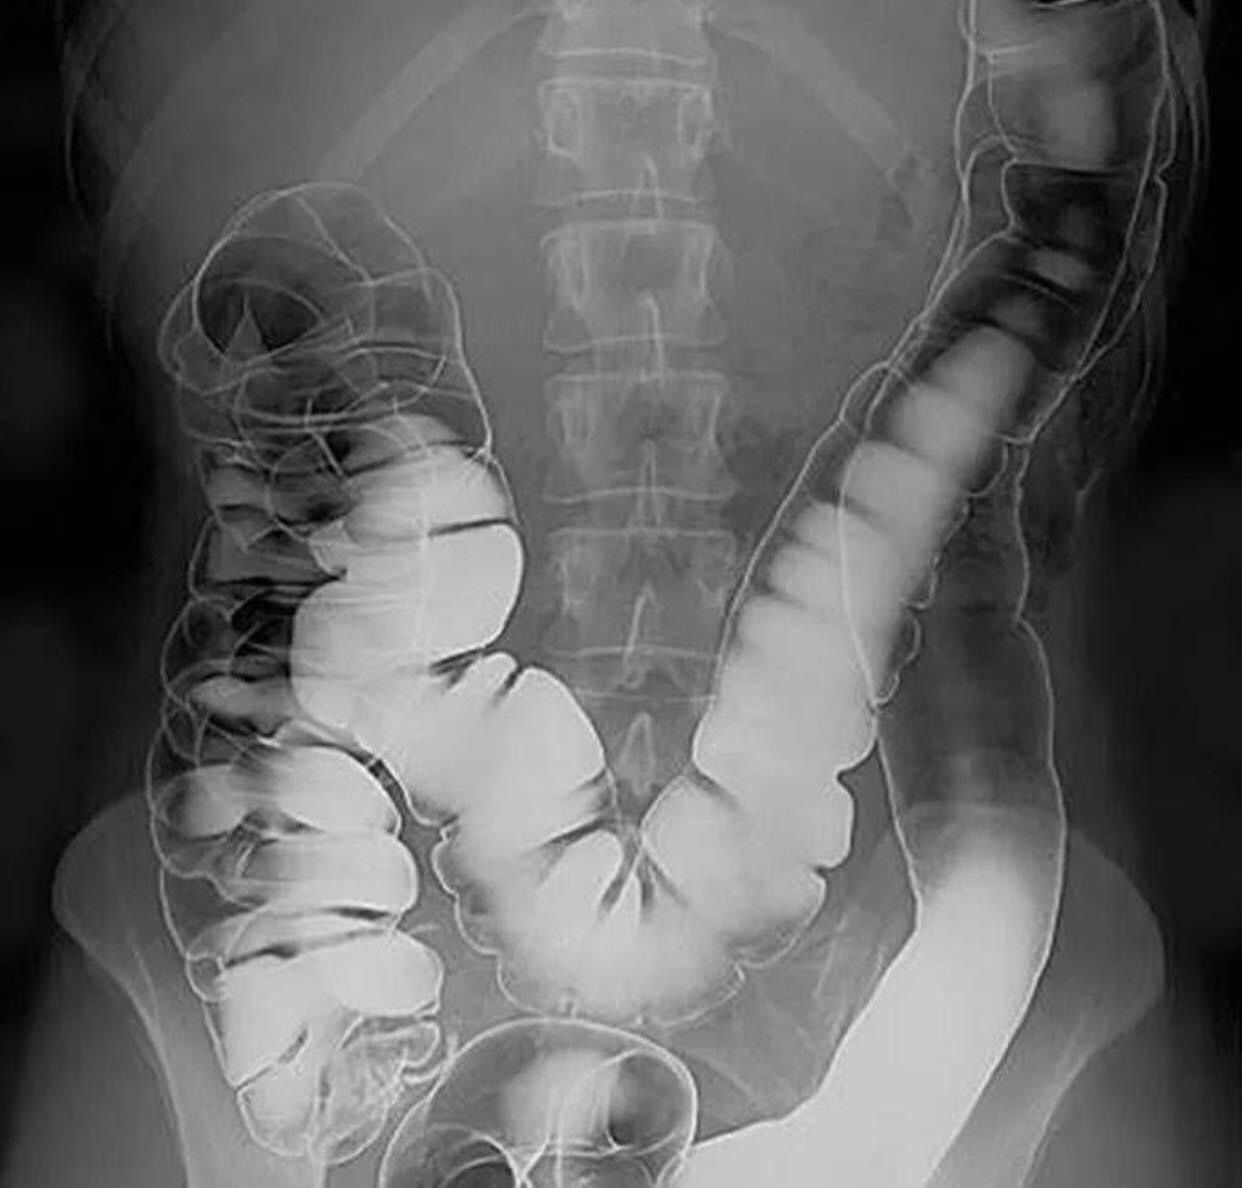

Bringing a whole new meaning to pain in the rear. Can you spot the pathology in this image? Shown here is an image of a patient who underwent rectal contrast to evaluate the large intestine. Although there are multiple types of contrast, a common agent is gastrografin. Gastrografin is water soluble, which makes it osmotically active. This means that the administration of rectal contrast will draw water into the lumen of the large bowel, making it an ideal choice to treat large bowel obstructions from constipation - a very common problem in older adults. Once contrast has been administered, an X-ray is taken, which can give various findings depending on the underlying pathology. In contrast (pun intended), Oral administration of gastrografin can help treat small bowel obstructions due to is osmotic activity as well. Alternative agents can also be chosen for rectal contrast such as sodium phosphate although sodium phosphate has been associated with higher rates of volume depletion and hypotension. Another classic use for rectal contrast is for the diagnosis of pediatric large bowel disorders such as Hirschprungs disease and meconium ileus or other causes of large bowel obstructions in adults. (Via Medicos.)